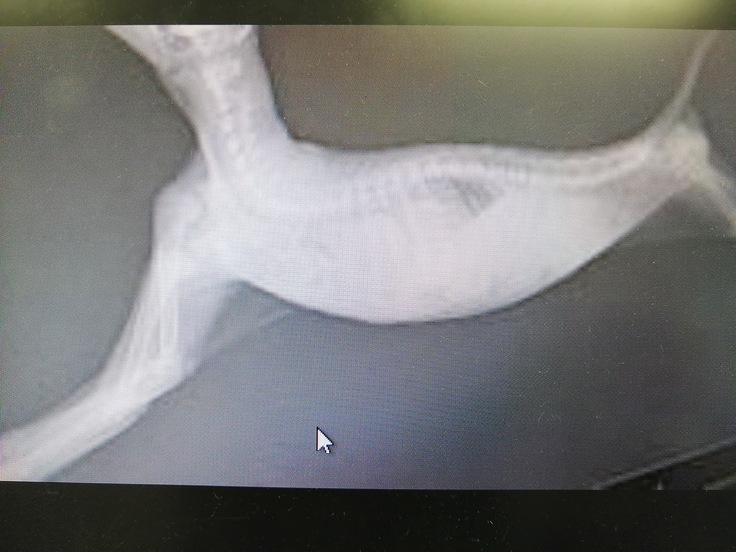

今回保健所より保護した猫は右後足に酷い怪我しておりましたのですぐ病院へ連れて行きました。

病院にて怪我の状態を確認したところ傷口の中からキツく巻きつけられ組織に食い込んだ紐のようなものが出てきました。

虐待により足を縛られどのくらいの期間を過ごしていたのかはわかりませんがハッピーの足は大腿部から足首までの皮膚がただれ、皮もめくれ、壊死した部分もかなりありました。

医師からは切断するか壊死した部分を剥ぎ取り治療を続け自己治癒力にて皮膚が再生するのを待つかの二者択一でした、人間によって傷つけられたのなら人間が元の姿に戻してあげたい、思い切り走り回れる健康な姿に戻してあげたいと思いプロジェクトを立ち上げました。

移植手術の手順は

①お腹に後足を納め縫合

②納めた足の下部を切開しお腹の皮膚と縫合

③納めた足の上部を切開、お腹の皮膚をはがし足全体に巻き縫合してお腹と足を分離させる

と3回の手術が必要となります。